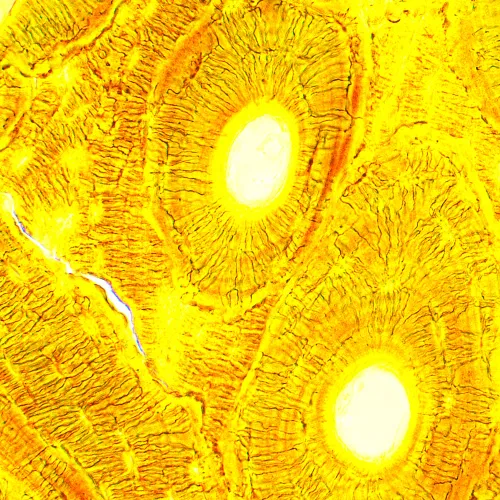

Il microscopio biologico MAGUS Bio 230B è uno strumento professionale per l’osservazione di campioni biologici in luce trasmessa. La principale tecnica di microscopia usata è quella in campo chiaro (immediatamente accessibile). È possibile usare anche tecniche di osservazione in campo oscuro, con contrasto di fase o luce polarizzata, ma richiedono l’impiego di accessori da aggiungere al microscopio. Questo microscopio è perfetto per le osservazioni in laboratorio e per la ricerca in campo medico, farmaceutico, forense, agricolo e vari altri campi.

Fotocamera full color con sensore CMOS SONY Exmor 2,1 MP digitale. Il sensore è prodotto sfruttando la tecnologia della retroilluminazione per ridurre la diffusione della luce e aumentare la sensitività della matrice (8935 mV a 1/30 s). La fotocamera produce immagini nitide e luminose anche in condizioni di scarsa illuminazione. Progettata per osservazioni a campo chiaro e scuro tramite obiettivi con ingrandimento 40x, 60x e 100x.

Gli obiettivi planacromatici forniscono immagini chiare, ricche di contrasto e di dettagli con aberrazioni minime. L’ingrandimento, usando degli obiettivi e degli oculari inclusi nella confezione, varia da 40x a 1000x, ma il limite superiore può essere aumentato con l’uso di oculari aggiuntivi. Le ottiche sono corrette all’infinito, il che significa che vari altri accessori possono essere inseriti lungo il cammino ottico.